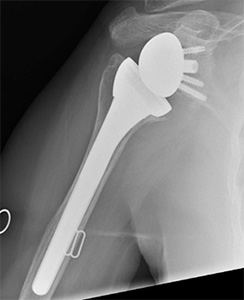

- Shoulder replacement: Some patients with large, long-standing cuff tears may develop arthritis between the humeral head and acromion (rotator cuff arthropathy). In such cases, replacement of the shoulder may need to be considered. The type of shoulder replacement may vary from a partial shoulder replacement (extended hemiarthroplasty) to a unique type of shoulder replacement which reverses the ball and the socket (see illustration below).